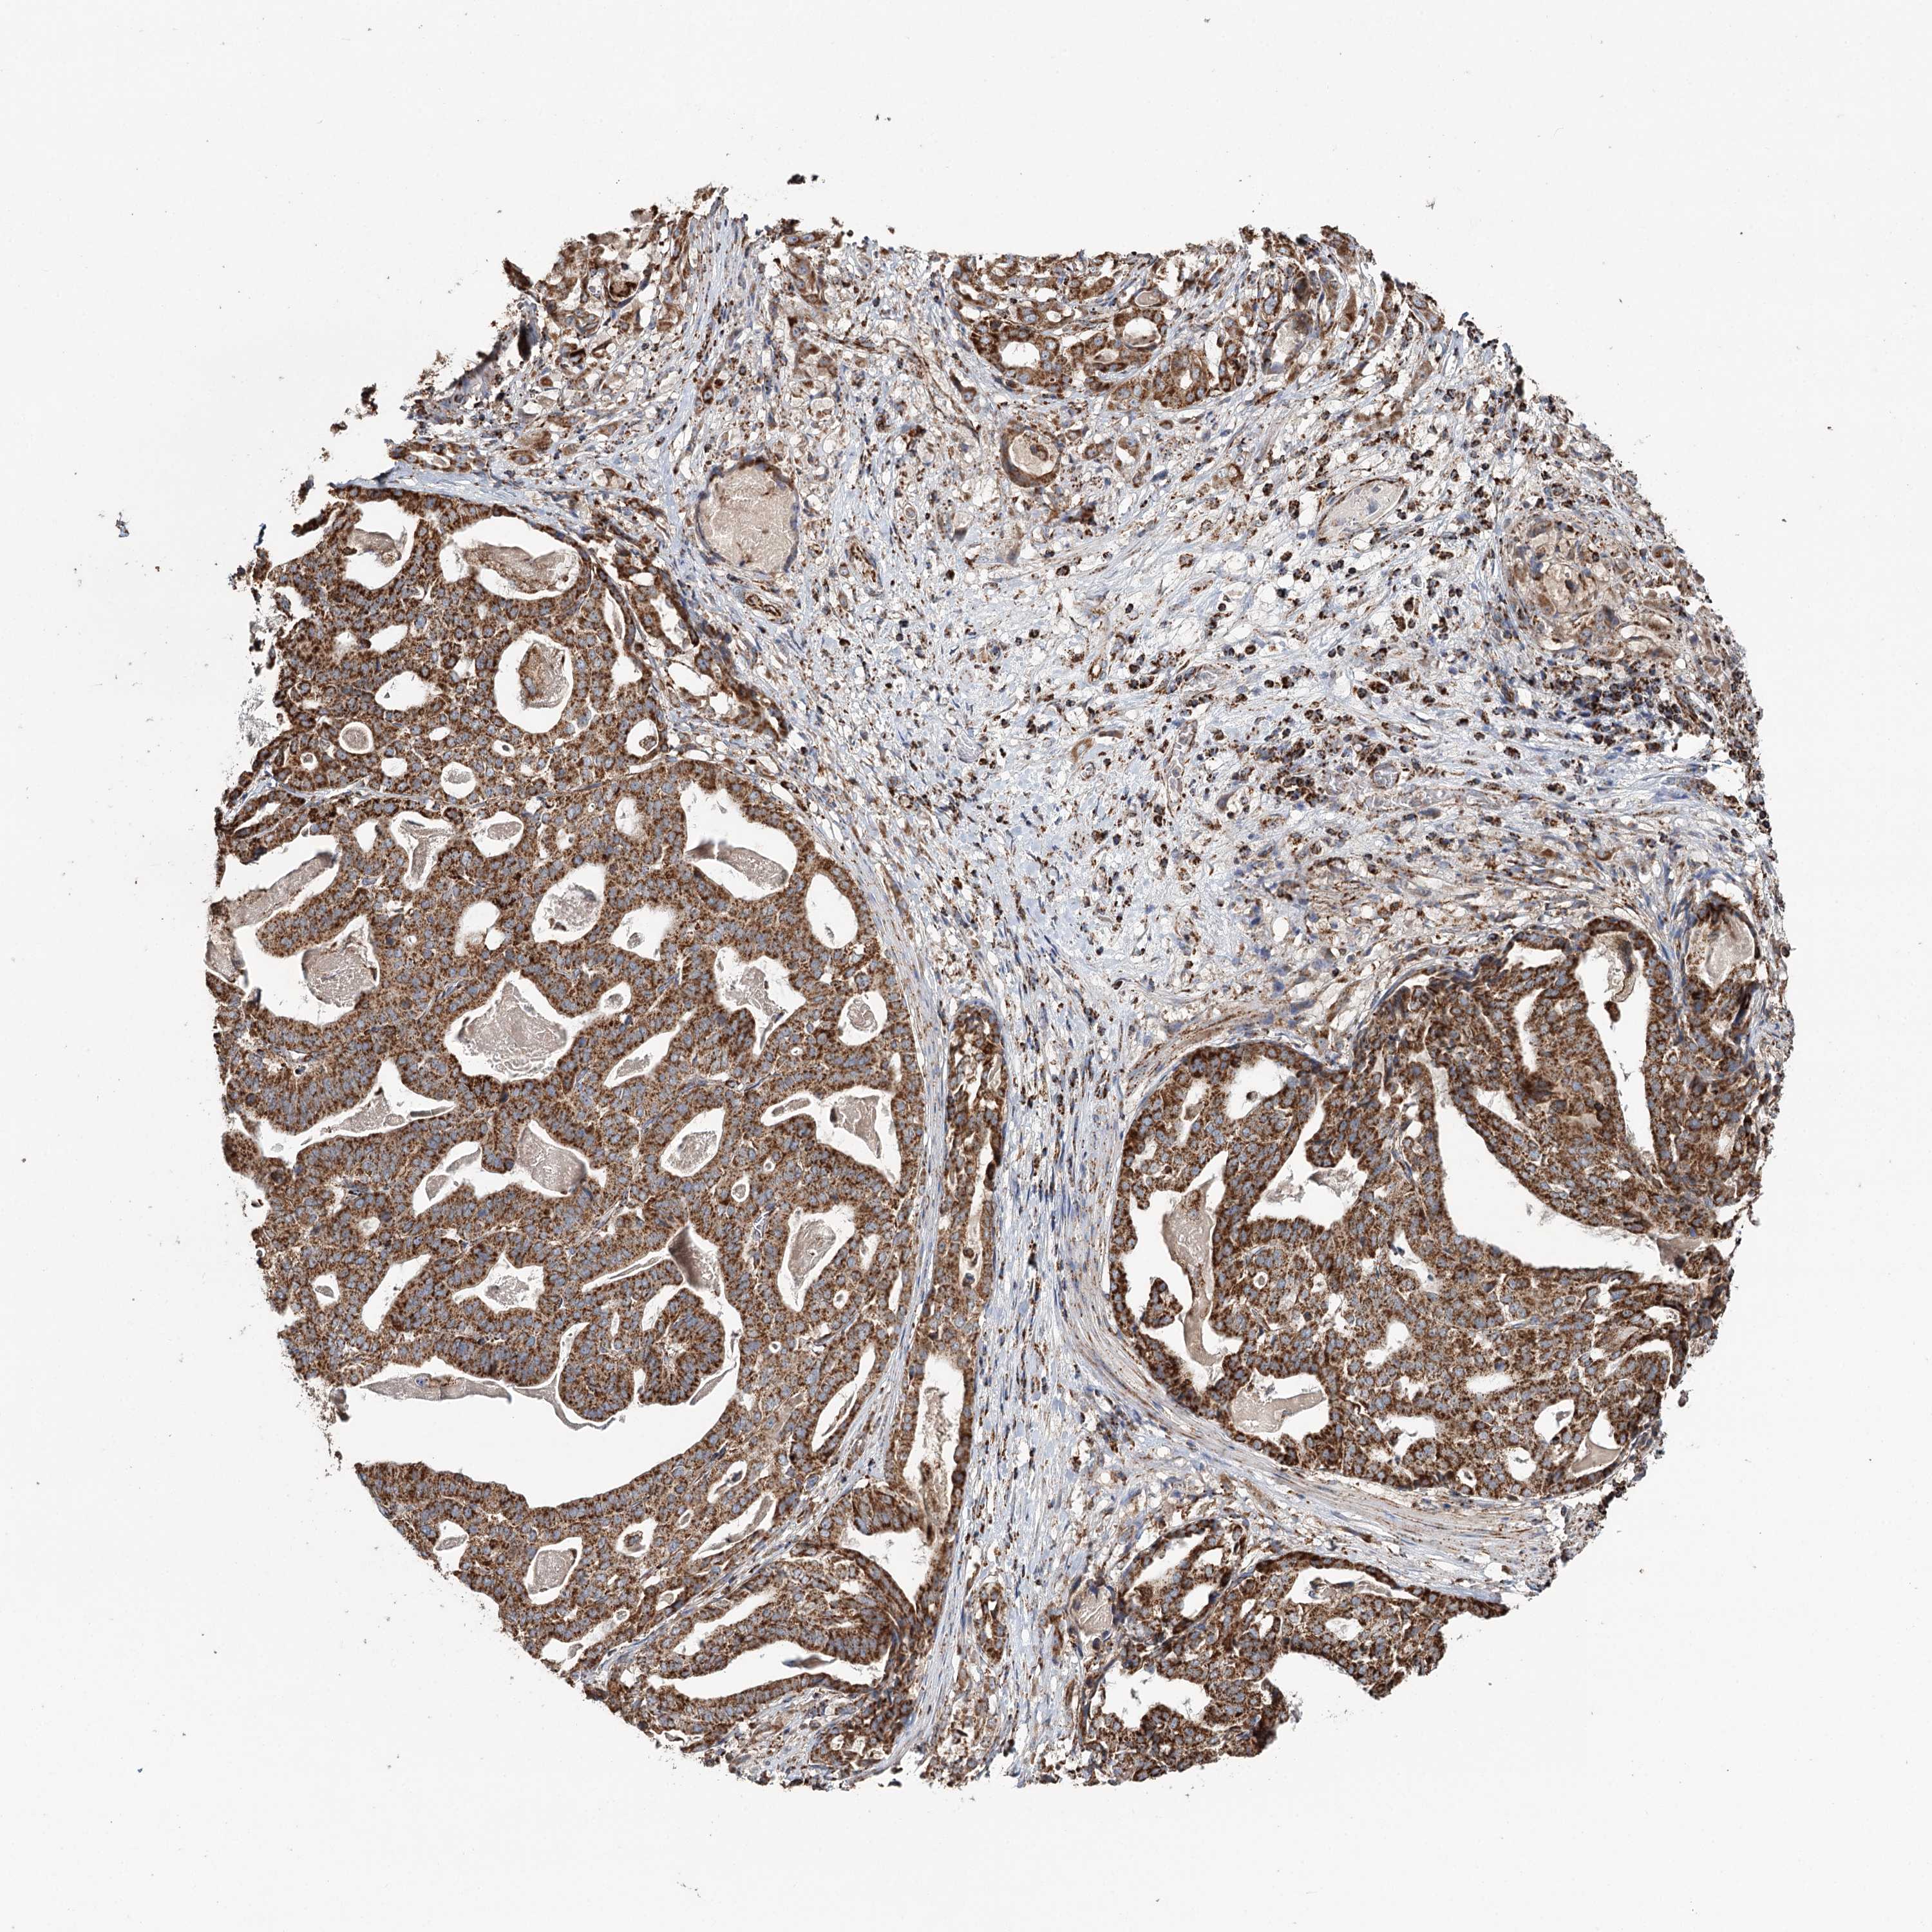

STOMACH CANCER - Protein expressioni

A mouse-over function shows sample information and annotation data. Click on an image to view it in a full screen mode. Samples can be filtered based on level of antibody staining by selecting one or several of the following categories: high, medium, low and not detected. The assay and annotation is described here.

Antibody stainingi

Antibody staining in the annotated cell types in the current human tissue is reported as not detected, low, medium, or high, based on conventional immunohistochemistry profiling in selected tissues. This score is based on the combination of the staining intensity and fraction of stained cells.

Each image is clickable and will lead to virtual microscopy that enables deeper exploration of all samples and also displays staining intensity scores, fraction scores and subcellular localization as well as patient and tissue information for each sample.

Antibody CAB037272

Staining

High

Medium

Low

Not detected

Intensity

Strong

Moderate

Weak

Negative

Quantity

>75%

75%-25%

<25%

None

Location

Nuclear

Cytoplasmic/membranous

Cytoplasmic/membranous,nuclear

Adenocarcinoma, High grade